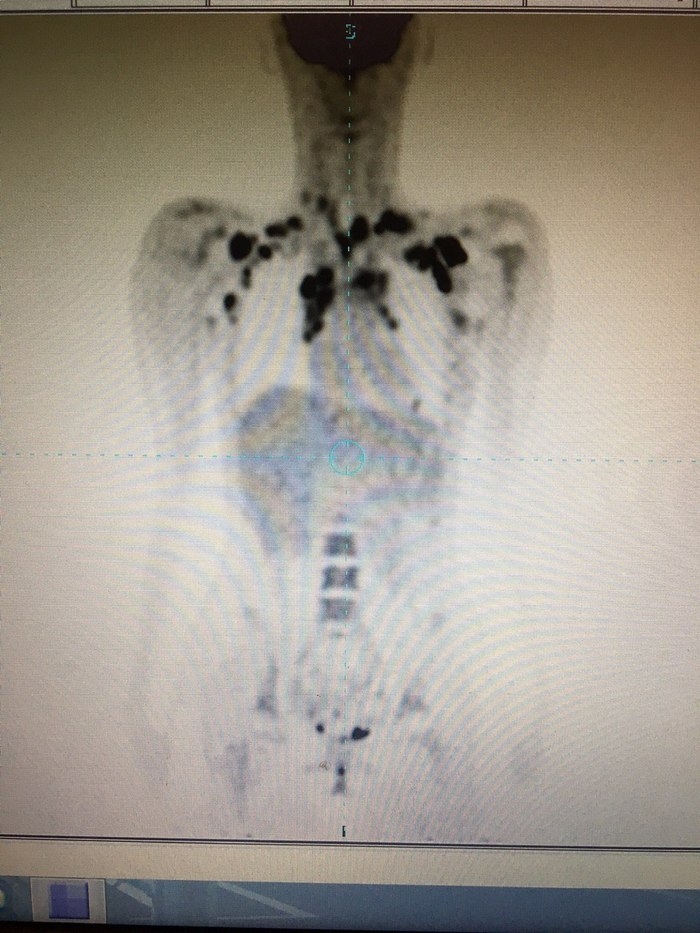

Лимфома Ходжкина. Пост 5, промежуточное

Все-таки я очень сухо и по фактам написала свои посты. На самом деле болезнь далеко не радужная тема, она меняет не только жизнь, но и сознание. Тот факт, что я отделалась минимальным количеством физических побочек - это прекрасно, а также, считаю, что это во многом заслуга врачей и гематологического отделения химиотерапии, где проходила лечение, им я бесконечно благодарна за оказанную профессиональную помощь. Конечно, как и многие другие услышав диагноз, да какой там диагноз..просто подозрения даже, я испытывала дрожь в коленках, немощь в сердце и отчаянное «как же так?!?», а слёзы катились из красных от натуги глаз. Боялась многих вещей, сильно переживала, что от меня отвернутся нужные люди. Помимо этого чувствовала себя с каждым днём все хуже и хуже физически, постоянная температура, ломота всего верхнего наддиафрагмального отдела (стоило походить часа 2-3). Вот что было изначально на первом пэт кт (чёрное сверху - это опухоль):